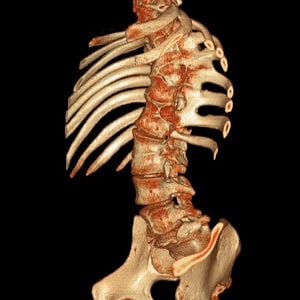

Выявить аномалии развития позвоночного столба может ортопед или хирург. При осмотре пациента врач отмечает искривления, нарушения осанки, вплоть до формирования горба. На рентгенографии во фронтальной плоскости две половинки позвонка суживаются без слияния по направлению к центру, образуя фигуру, напоминающую крылья бабочки.

Компьютерная и магнитно-резонансная томографии позволяют оценить состояние межпозвонковых дисков, нервных стволов, сосудов, спинного мозга. Эти методы используются для уточнения диагноза уже после того, как проведен хирургический и неврологический осмотр пациента.